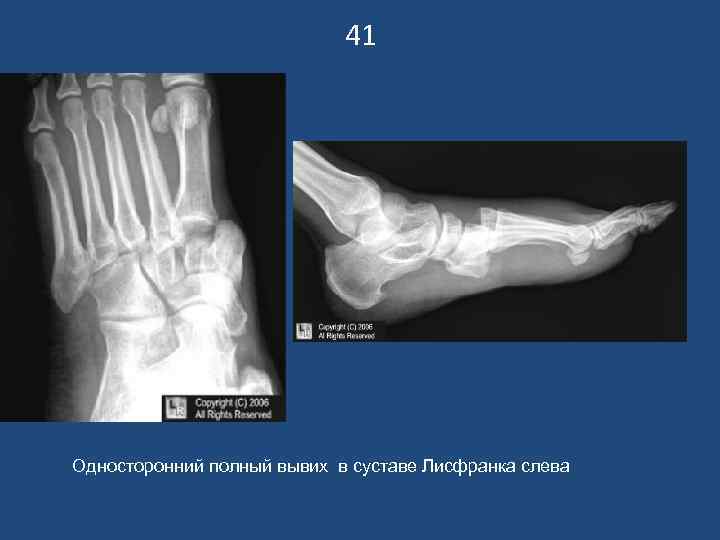

41 Односторонний полный вывих в суставе Лисфранка слева